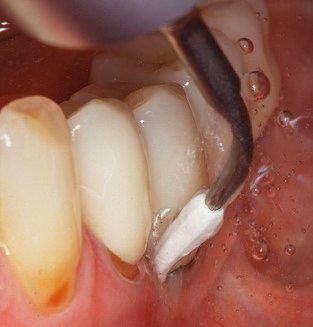

Good illumination of the working field facilitates the process considerably. The system used by the authors achieves this thanks to a 5x LED ring integrated in the handpiece. Naturally, a range of working tips for different indications is also offered. A straight, universally employable tip is the basic instrument required for machine cleaning of natural teeth (Fig. 5a and b). Curved tips, which allow access to exposed furcations, are also available for hard-to-reach areas in the posterior region (Fig. 6).

Of course, working tips for the cleaning of implant surfaces are also indispensable for SPT in patients fitted with implants. The implant cleaning attachment on the system used here is characterised by its tapered, hexagonal design. This design allows light, atraumatic penetration of the peri-implant pocket and displays a good cleaning performance (Fig. 7).

Following machine cleaning of the tooth and implant surfaces, the surfaces of the natural teeth are cleaned manually using standard hand instruments. When performing manual cleaning, particular attention must be given to maintaining the correct angle of application, appropriate sharpness, good support and working with the curette from apical to coronal. Either titanium or carbon curettes should be used for post-cleaning of the implant structures (Fig. 8). In addition to the use of ultrasonic devices, power jet devices can also be used in conservative dentistry. However, it must be taken into consideration that these procedures are not suitable for removing hard deposits and thus they cannot replace the use of hand instruments and ultrasonic instruments completely. In all cases, cleaning is followed by mechanical polishing of the accessible tooth and implant surfaces with polishing cups and polishing compounds (Fig. 9).